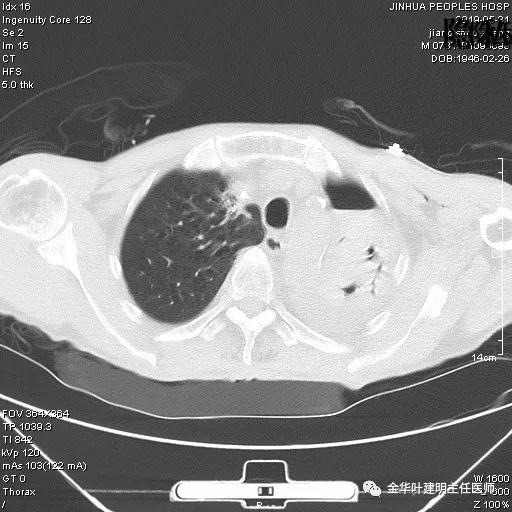

患者,男性,73岁,金华人。因“咳嗽咳痰伴胸闷2月,检查确诊左肺癌1周”入院。气管镜: 气管支气管内较多脓性分泌物,左肺上叶前段管腔新生物,局部活检、毛刷。气管镜病理:(左肺活检)鳞癌。阅胸部CT见左上叶开口处新生物,考虑需左上叶袖式切除及淋巴结清扫。具体CT表现如下:

考虑左侧大量胸腔积液,遂进一步胸部CT检查:

以上是肺窗表现,下面为纵隔窗影像: